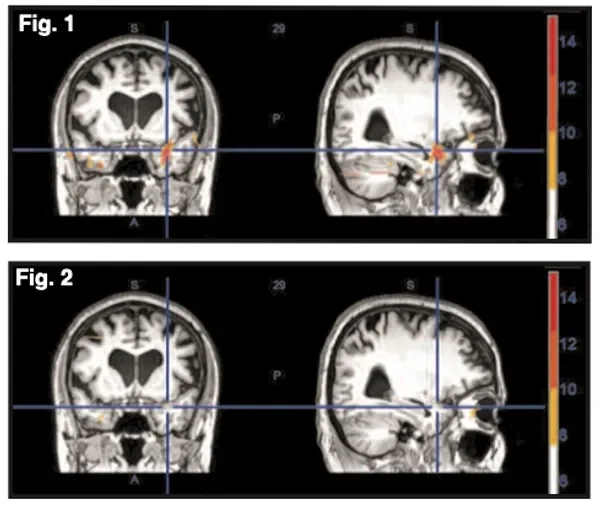

Before & After: NET’s Impact on the Brain’s Stress Center

There is now quantifiable evidence as to ‘why’ patients feel better when treated with NET, and the dramatic pre- and post- treatment changes can be seen in fMRI brain images.

A recently published study examined the effects of NET on brain physiology in patients experiencing stress symptoms.